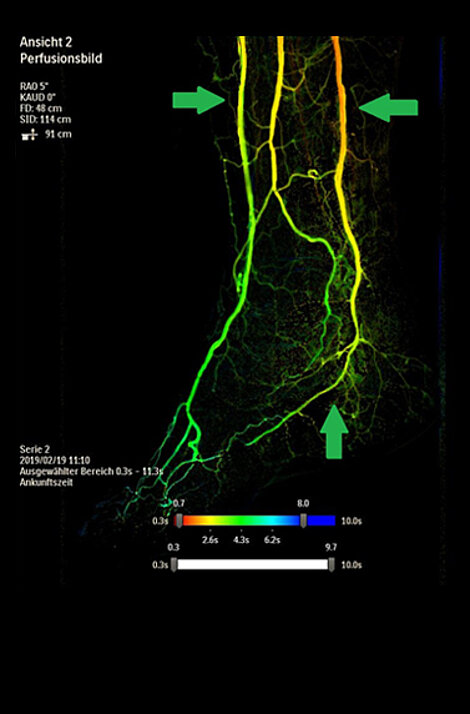

Unterschenkel- und Fußarterien bei diabetischer Angiopathie

Vorher

Verschluss der Arterie bei diabetischem Fußsyndrom (links: Unterschenkel, rechts: Fuß).

Nachher

Erfolgreiche Rekanalisation der Fußarterien.

1-Gefäßversorgung der Arteria fibularis.

3-Gefäßversorgung im Unterschenkel.